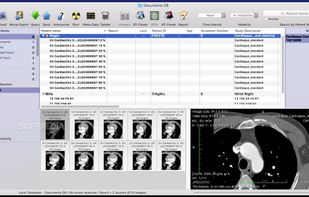

Weasis is a multipurpose standalone and web-based DICOM viewer with a highly modular architecture. It is a very popular clinical viewer used in healthcare by hospitals, health networks, multicenter research trials, and patients.

Weasis is a multipurpose standalone and web-based DICOM viewer with a highly modular architecture. It is a very popular clinical viewer used in healthcare by hospitals, health networks, multicenter research trials, and patients.